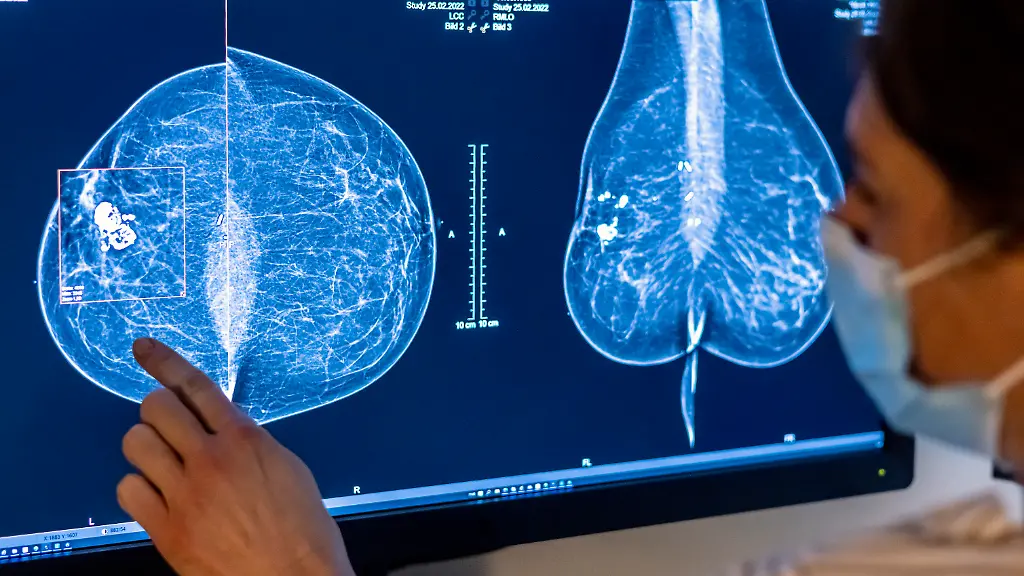

Bisher wird nur Frauen bis zum Alter von 69 Jahren eine regelmäßige Früherkennung für Brustkrebs per Röntgen-Untersuchung angeboten. Die Altersgrenze wird jetzt jedoch angehoben - davon können Millionen Frauen profitieren.

Ausweitung der Brustkrebs-Früherkennung: Künftig dürfen Frauen im Alter bis 75 Jahre an dem Screening teilnehmen. Das sieht eine novellierte Verordnung des Bundesumweltministeriums vor, die an diesem Mittwoch in Kraft tritt. Zusätzlich rund 2,5 Millionen Frauen haben durch die Ausweitung Anspruch auf eine Teilnahme, wie der Gemeinsame Bundesausschuss mitteilte, das oberste Entscheidungsgremium über Leistungen der Krankenkassen im Gesundheitswesen.

Bislang war es Frauen nur bis 69 Jahren erlaubt, an den Röntgen-Untersuchungen teilzunehmen. Ab Juli können sich auch Frauen zwischen 70 und 75 zum Mammografie-Screening anmelden. Der Bundesausschuss hatte die Altersgrenze im vergangenen Jahr angehoben. Die nun erteilte Strahlenschutz-Zulassung sei die letzte Voraussetzung für das Inkrafttreten, so der Ausschuss. Frauen im Alter von 70 bis 75 könnten sich folglich ab 1. Juli bei den sogenannten Zentralen Stellen für einen Untersuchungstermin in einer wohnortnahen Screening-Einheit anmelden.

Umweltministerin Steffi Lemke sagte: "Durch die erweiterte Altersgrenze können künftig noch mehr Frauen zu den Untersuchungen gehen." Das finde hoffentlich großen Anklang. "Brustkrebs-Früherkennung kann eine echte Lebensretterin sein." Brustkrebs ist mit jährlich rund 70 000 Neuerkrankungen die häufigste Krebserkrankung bei Frauen in Deutschland. Seit 2009 wird Frauen zwischen 50 und 69 Jahren alle zwei Jahre eine Röntgen-Untersuchung zur Früherkennung angeboten.